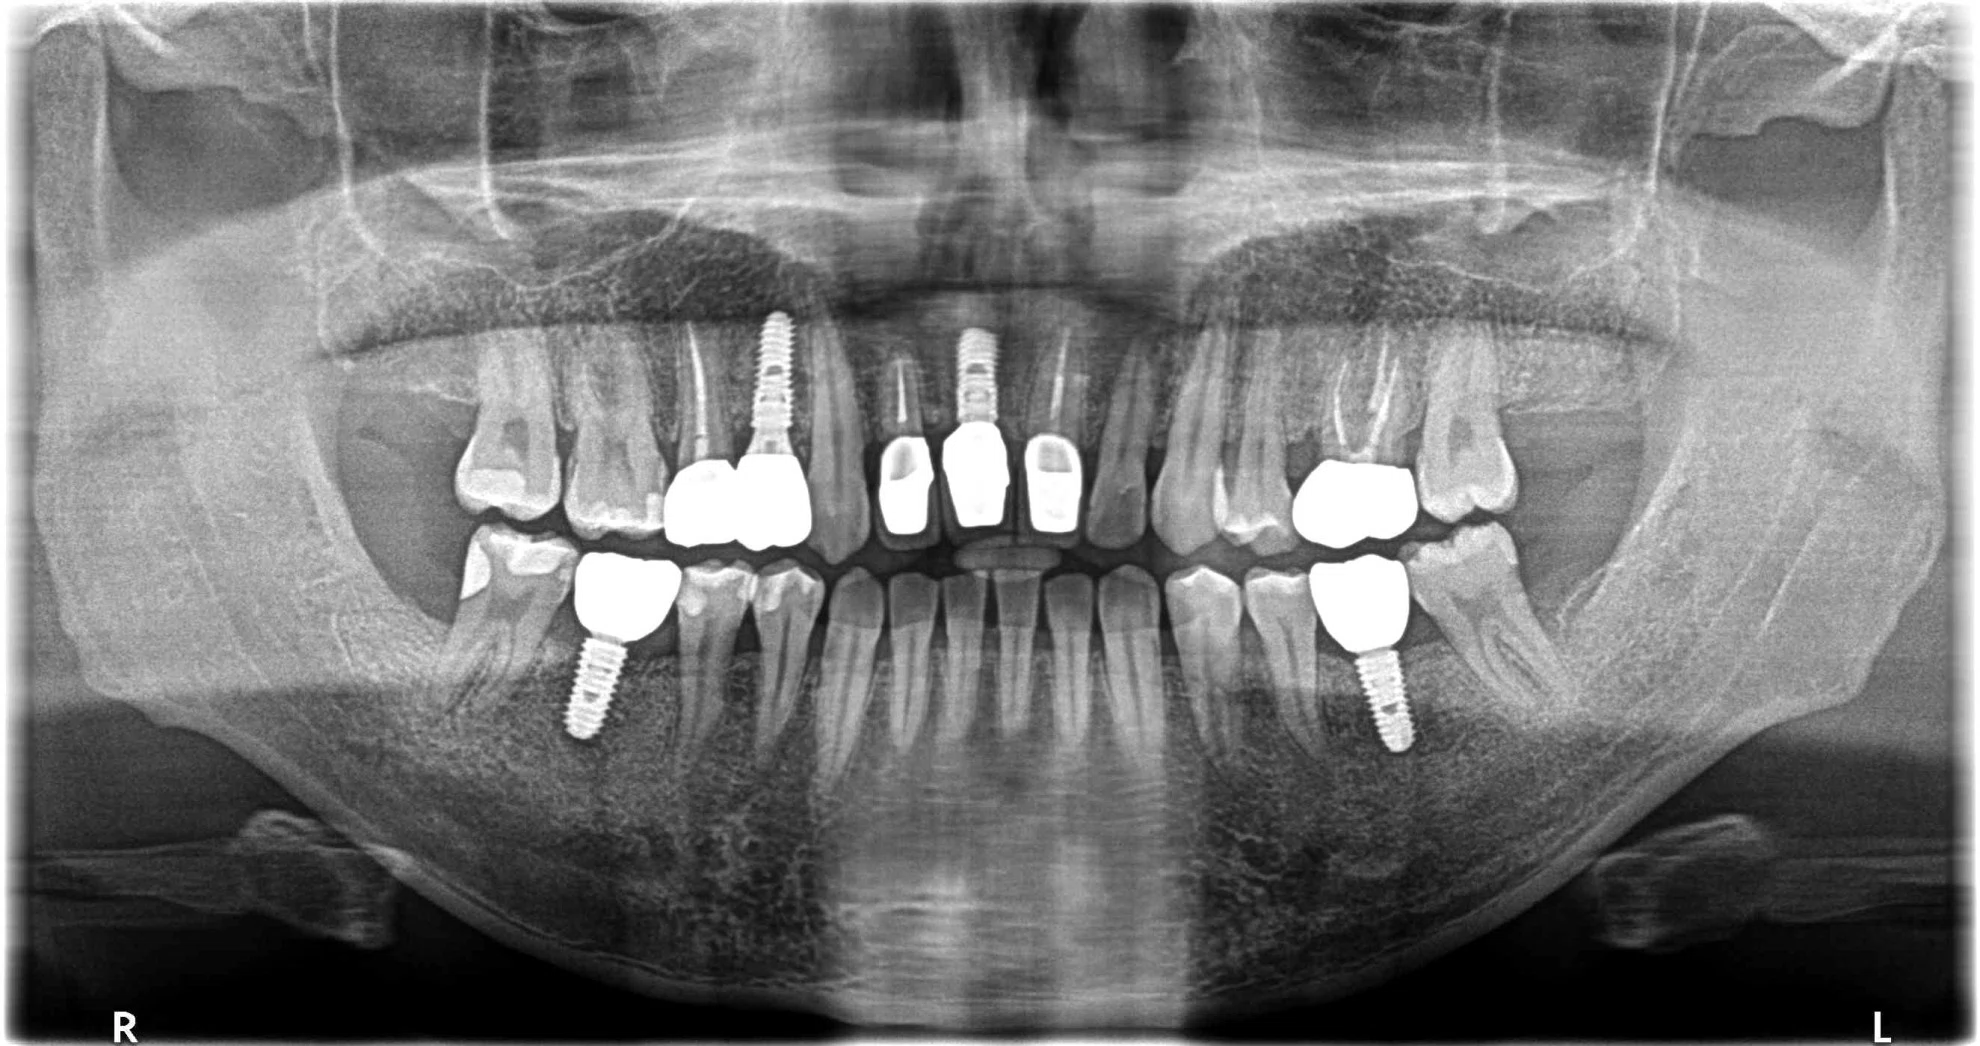

後牙區觀察到多處缺牙,可能伴隨齒槽骨條件的考量。成功植入多顆人工牙根 (植牙),X光片顯示植體位置精準,骨整合情況良好,為恢復咀嚼功能奠定堅實基礎。

前牙區可見多顆牙齒的齒質狀況與根尖健康需要處理。根管治療成功完成,並搭配全瓷冠進行修復,重建了牙齒的形態與強度。

結合術前 CBCT 3D 掃描與手術導板,實現「導引式植牙」。

將植牙手術的微創性、精準性提升到極致,準確避開重要神經與血管,保護周圍骨組織。從 X 光片可見,人工牙根植入位置理想,能最大化後續假牙的受力穩定性,快速恢復患者的咀嚼功能